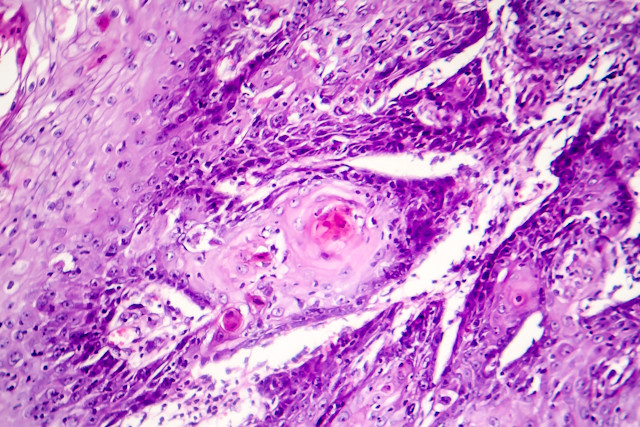

Histology

SCC is a malignant epithelial tumour of keratinocytes arising most commonly in sun-damaged skin. The vast majority of cases are associated with pre-existing actinic (solar) keratosis, squamous cell carcinoma in situ, or both. SCCs account for nearly 30% of non-melanoma skin cancers.

Some SCCs may be associated with human papillomavirus, chronic inflammation or radiation therapy.

From a histological point of view, these lesions may be well differentiated, moderately differentiated or poorly differentiated. The degree of differentiation is an essential marker of progression, risk of metastasis and prognosis. Many lesions display areas of varying degrees of differentiation, however, the worst area is to be considered when finally grading the lesion. It is the least differentiated area that ultimately determines the management and prognosis.

SCC with focal basaloid differentiation or basosquamous carcinoma, is regarded as a moderately differentiated lesion. Poorly differentiated SCCs are characterised by the absence of keratinisation. SCC may be slow or fast growing. In some cases, significant clinical changes may be evident within months, or even weeks.